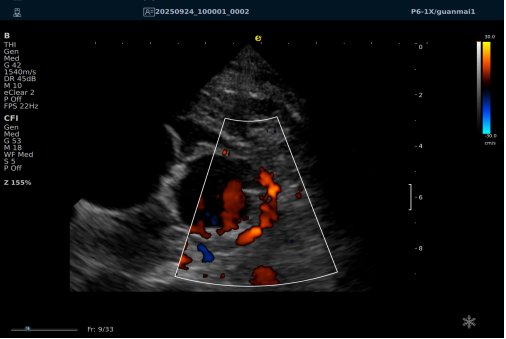

以下为逸超医疗(ESI)设备采集的冠脉图像,清晰展示了其在二维成像、彩色多普勒及频谱多普勒方面的表现:

左右滑动查看更多

心脏冠脉超声